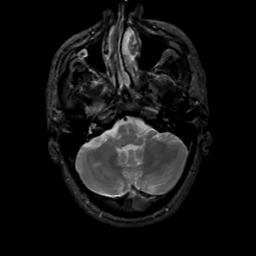

MR Study #2, February 17, 1991 -- Slice #10

[Home][Help][Clinical][Tour 1][Tour 2] Slice 10